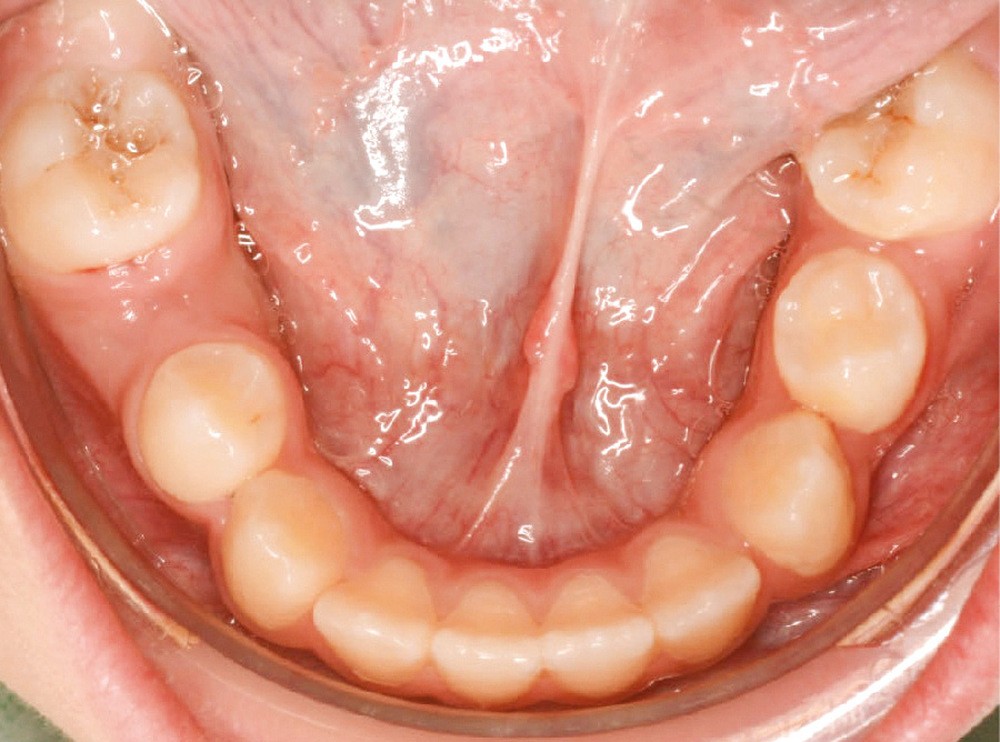

Lina, 8 ans et 5 mois, nous est adressée en consultation d’orthodontie dans le service de médecine bucco-dentaire de l’Hôpital Bretonneau en transfert avec absence des 2 prémolaires du secteur 1, alors que 44 et 45 sont présentes et que cette dernière manque de place pour faire son évolution sur l’arcade (fig. 1 et 2).